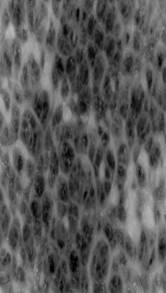

Инструментальные методы. Ультразвуковое высокочастотное исследование кожи: поверхность кожи в зоне патологического очага правой голени (на границе с кожей, свободной от высыпаний) деформирована кнаружи, визуализируются множественные образования эпидермального типа округлой и плоской форм размерами 0,5–1,5 см. Микрорельеф эпидермиса в зоне патологии значительно усилен. Толщина эпидермиса 0,5–0,7 мм. Субэпидермально – анэхогенная зона, без структурных элементов до 0,5 мм. Толщина дермы в проекции элементов 1,5–2,8 мм (на неизмененном участке – 0,6 мм), структура дермы смазана, имеет более низкую эхогенность. Граница дермы с подлежащими тканями имеет размытый характер, не визуализируется нижний контур образований (рис. 2).

Рис. 2. Ультразвуковое исследование кожи в области сосочковых разрастаний

Примечательно, что для диагностики и дифференциальной диагностики карциноидного папилломатоза кожи Готтрона впервые были использованы высокотех-нологичные методы: дерматоскопия, при которой была отмечена типичная морфологическая картина в виде образований сосочковой структуры розово-красного цвета с полиморфными сосудами, между которыми визуализировались десквамация эпидермиса и гомогенные массы белого цвета; ультразвуковое исследование, показавшее деформацию и усиление микрорельефа эпидермиса в зоне патологии, при этом гипоэхогенные участки неправильной формы с неоднородной структурой и неровным контуром без акустической тени, характерные для злокачественных новообразований кожи, не определялись; а также гистологическое исследование, выявившее выраженную псевдоэпителиоматозную гиперплазию эпидермиса без признаков атипии, папилломатоз и акантоз.